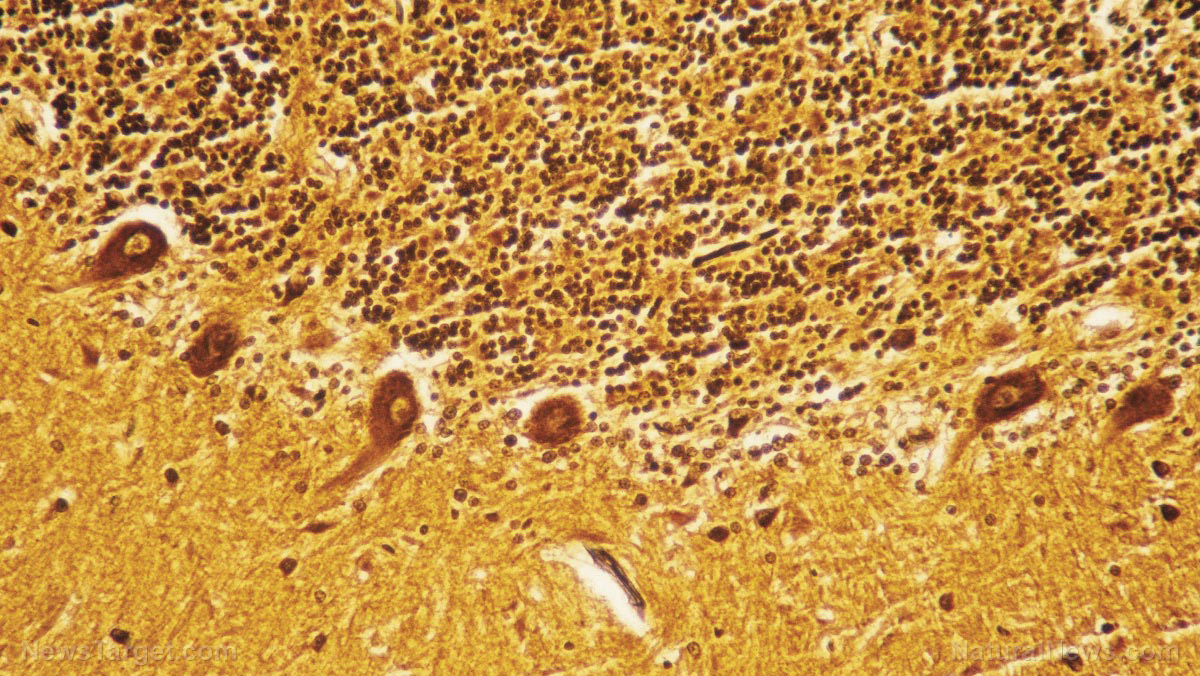

At the end of the treatment period, the mice were sacrificed so that the researchers could analyze their blood and brain tissue using a variety of tests such as flow cytometric, immunohistochemical staining, and immunofluorescence.

Based on the results of the CMU analysis, catalpol improved neurological functions in EAE mice by preventing inflammatory cells from entering the brain tissue and halting the destruction of the myelin sheath. Catalpol also decreased the amount of T helper 17 (Th17) cells in the blood, which can trigger inflammatory responses in the brain.

Furthermore, catalpol boosted the production of myelin basic protein, the building blocks of the myelin sheaths that surround healthy brain cells. It also encouraged the expression of the nerve-glial antigen that serves to bind proteins together into useful structures.